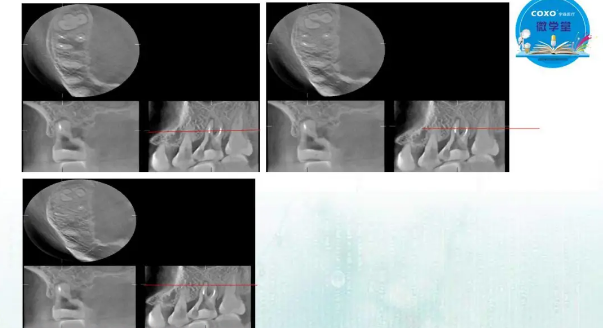

主講:孫書昱

主任醫(yī)師,牙體牙髓副主任, 廣東省口腔醫(yī)院牙體牙髓科 主任醫(yī)師。2003年碩士研究生畢業(yè),研究方向?yàn)檠荔w牙髓病學(xué),擅長(zhǎng)于牙體牙髓病的診斷、齲齒、牙髓炎、根尖周病的治療以及前牙美容修復(fù)。